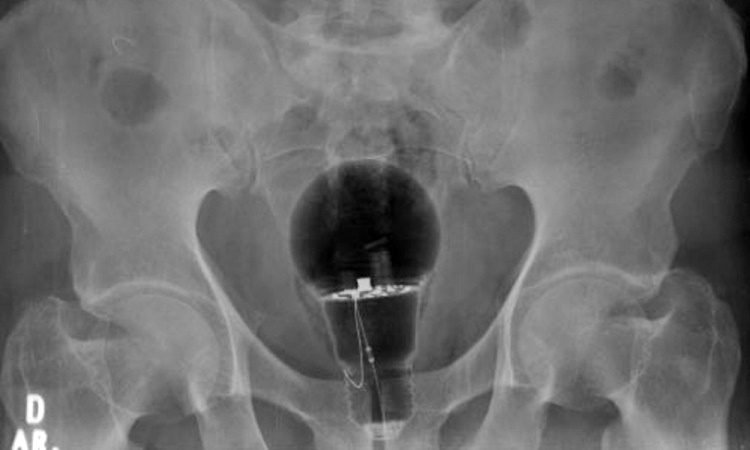

“O objeto não era palpável ao toque retal. Material de corpo estranho”, escreveu no Twitter o gastroenterologista Julian Pylori, que divulgou uma imagem do raio-x. A TV Azteca informou que o objeto era de plástico e, assim, não estourou dentro do corpo do homem.